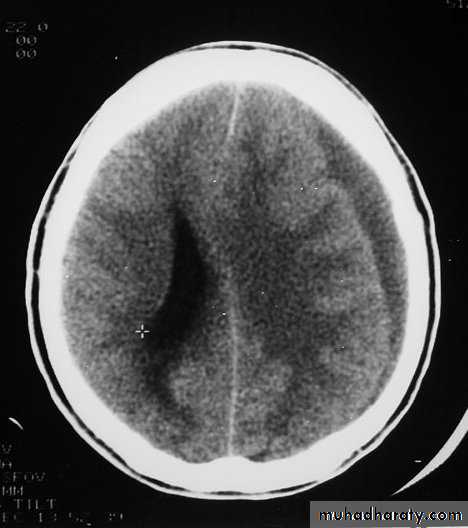

1. Brain Oedema (Cerebral Swelling)

Neurosurgery